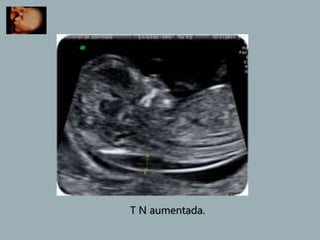

T N aumentada.